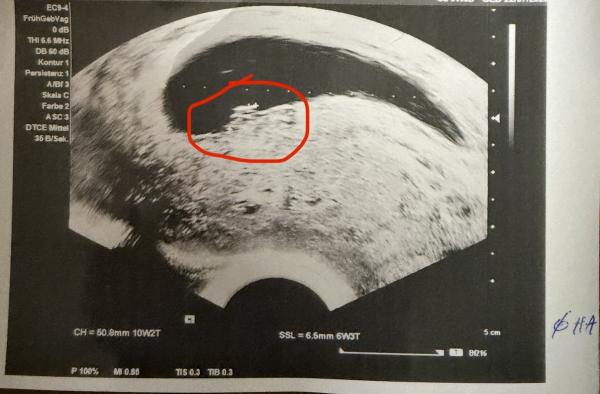

Heyy ihr, Ich hab eine Frage ob sowas in der Art hier auch schon jemand erlebt hat. Rechnerisch (letzte Menstruation 15.10.) müsste ich mich nun in etwa in der SSW 10 befinden. Letzte Woche und die Wochen davor beim Frauenarzt war auf dem Ultraschall außer der Fruchthöhle nichts zu sehen und es wurde schon immer von einem Windei gesprochen. Nun war ich heute wieder und plötzlich war auf dem Bild etwas zu sehen (siehe Bilder). Ich weiß es sieht nach nichts aus und wäre auch viel zu spät, aber gibt es sowas? Man sieht auch nicht viel auf dem Bild. Die FA meinte dann aber, dass jetzt doch iwas da ist, man sich aber nicht all zu viel Hoffnung machen solle.. hat jemand schon mal eine ähnliche Erfahrung gemacht? Ist iwie komisch für mich gerade.. LG und besinnliche Tage

Hallo, ja leider hatte ich so etwas vor 5 Monaten, ein sogenanntes Windei. Wann sollte du denn wieder zur Kontrolle?